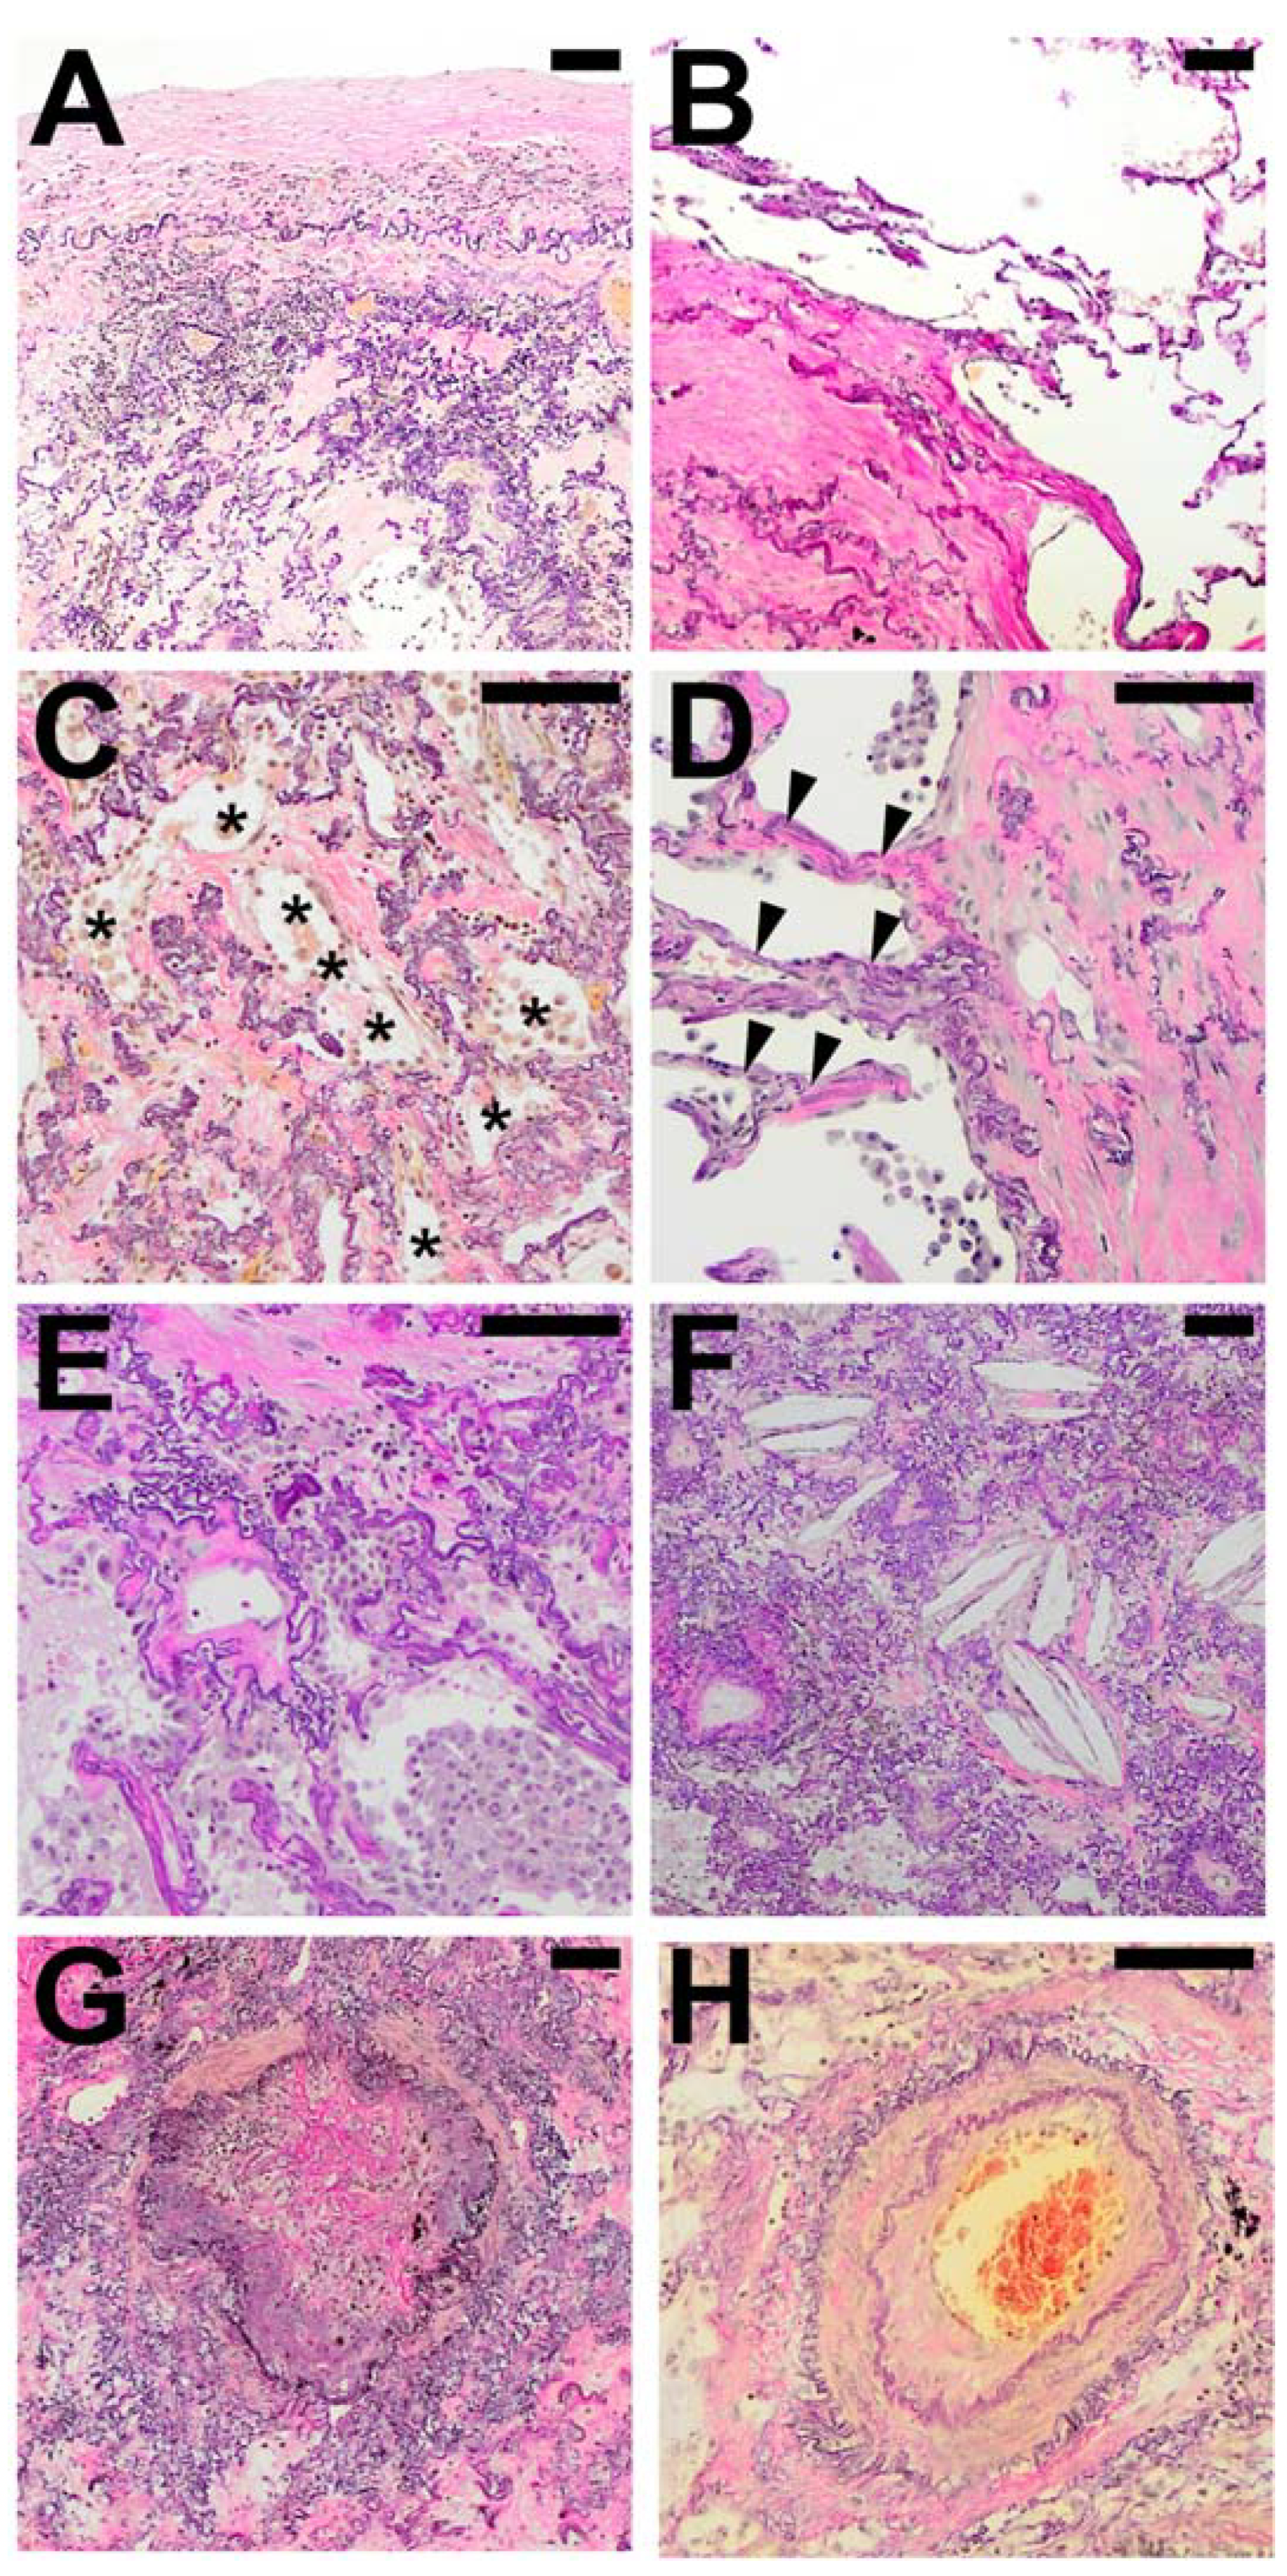

Within areas of typical AFE, the pattern of intra-alveolar fibrosis/fibrotic obliteration was classified as coarse fibrillary if broad hyalinised bundles of collagenous fibres (usually ~2 µm in diameter) were present and as fine fibrillary if delicate, mostly curled fibres were demonstrable. The presence of anthracophages and lymphoid aggregates was noted as well as an increase in cellularity with diffuse infiltration of lymphocytes or the presence of an increased number of mesenchymal cells such as (myo) fibroblasts in the obliterated alveolar lumen (see Figure 1).

In the majority of cases (67%) both coarse and fine fibrillary fibrosis could be detected, in the other cases either only fine fibrillary or only coarse fibrillary fibrosis (20% and 13% respectively) were detectable. Features found regularly in areas of AFE were aggregates of lymphatic cells (73%), often at the leading edge of the remodelling process (see Table 4). These appear well circumscribed, organized in an organoid manner, sometimes contain specialized vessels with the appearance of highly endothelialised venules (HEV) and can be distinguished from a diffuse infiltration of the AFE lesion by lymphatic cells which can be observed in approximately 30−40% of cases. Macrophages containing phagocytosed anthracotic pigment can be detected in 53% of total cases and appear less frequently in patients of the HSCT group (14%). Typical fibroblastic foci (FF) could be detected in 11% of cases. Overall, the areas of AFE showed similar morphological characteristics in all investigated groups. PAC showed overall less cellular mesenchymal (0%) and lymphatic (7%) infiltration when compared to the PPFE and PPFE-like cases (45% and 45% respectively).

Figure 1. Typical histological patterns of alveolar fibroelastosis (AFE). (A) Typical AFE is characterized by a complete obliteration of the alveolar lumen with collagenous material with formation of either coarse (B) or fine (C) fibrils. In some cases, aggregates of macrophages containing anthracotic pigment can be observed (D). Lymphoid aggregates are a common finding in or at the border of AFE lesions (E). Increased cellularity with presence of mesenchymal cells (F) or lymphocytes (G) can be observed in the fibrotic areas to a variable degree. All images are elastic van Gieson stainings. Scale bars are 100 µm each.